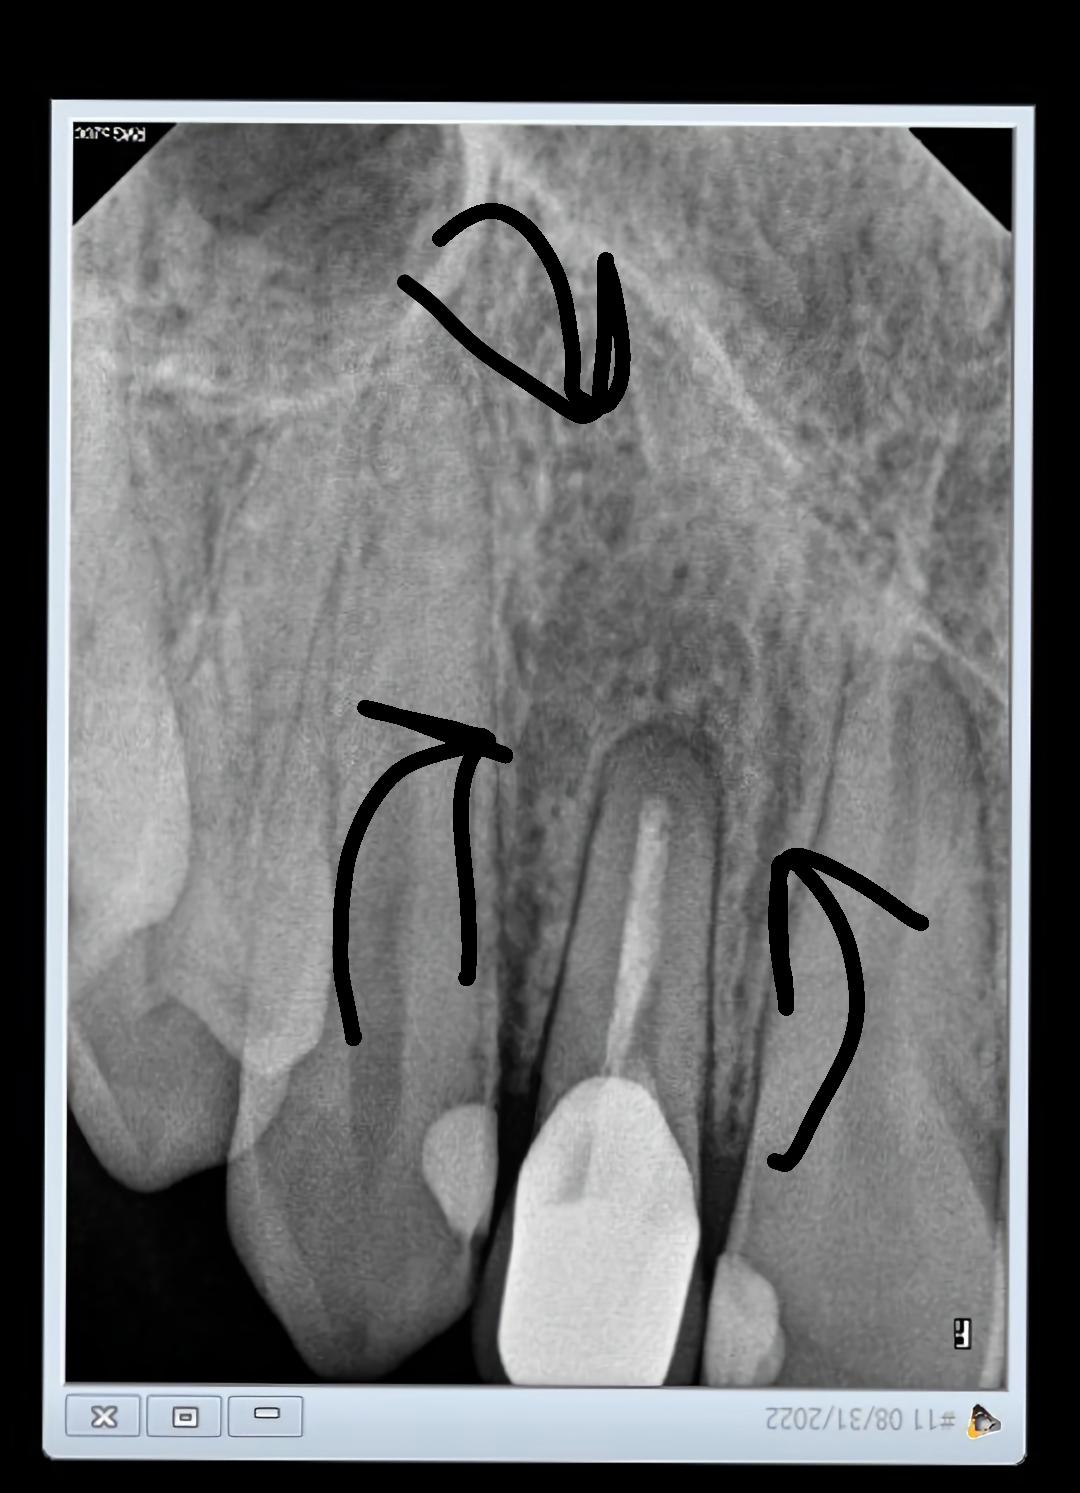

This tooth is a retreated root canal that started aching after a year Why Did My Dentist Give Me Amoxicillin Your dentist also might give you antibiotics to make sure the infection doesn’t spread to other teeth or other parts of your body. A tooth infection can start without symptoms, so good dental hygiene is important. The length of time it takes for a patient to see results is determined by the. Left untreated, they can also spread to nearby. Why Did My Dentist Give Me Amoxicillin.